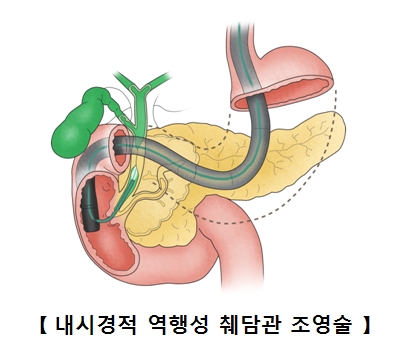

따라서 영상의학적 검사에서 담낭암이 의심되면 조직 검사 없이 곧바로 수술과 같은 치료를 시행합니다. 간내 담관이나 총담관의 침범을 알아보기 위해 내시경적 역행성 췌담관 조영술(ERCP)을 실시합니다.